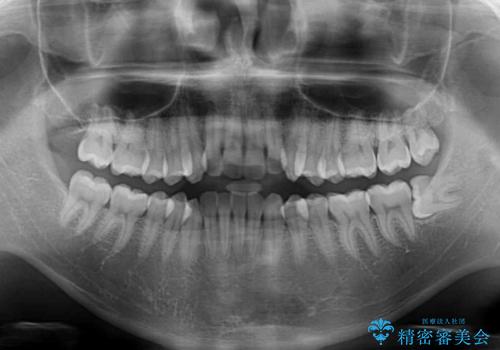

- 前歯のデコボコと若干口元が突出していることを気にして来院された患者様です。

全体的に軽微な叢生が認められ、口元もやや前方に突出していたため、インビザラインでのIPR(歯と歯の間を削る)と歯列全体の後方移動によって歯並びを整えることとしました。

上下ともに歯列の幅が狭かったため、側方に拡大することで前歯のデコボコや突出感を解消するためのスペースを獲得することができました。